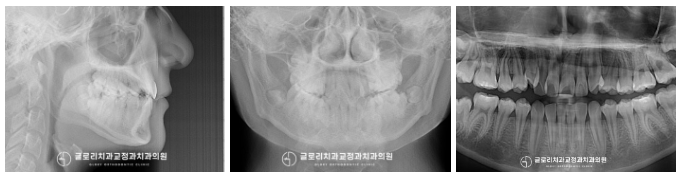

방사선 촬영을 통해 골격 검사를 했을 때

다행히 비대칭이나 다른 문제들은

발견되지 않았습니다.